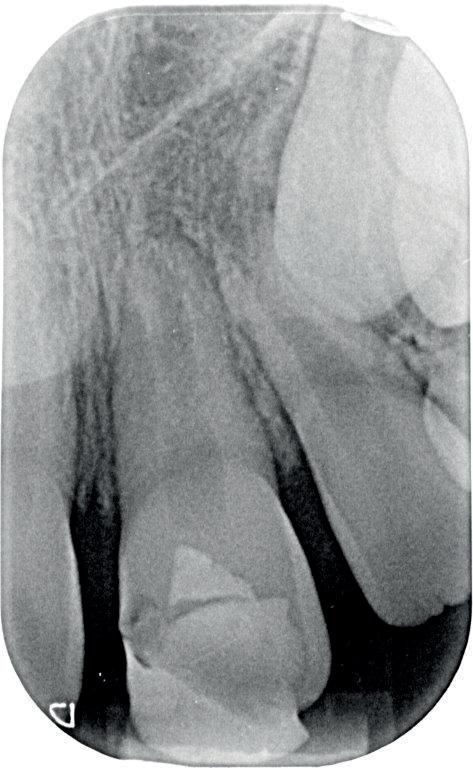

Voordat je aan een wortelkanaalbehandeling begint, zorg je voor (of maak je) een goede beginfoto waar het te behandelen gebitselement volledig op staat afgebeeld. Deze foto geeft essentiële informatie: de grootte van de pulpakamer en de ligging ervan; het aantal en de vorm van de wortels en de breedte van hun wortelkanalen en de lengte van de wortels. Hiermee kan je de DETI-score bepalen en de moeilijkheidsgraad inschatten. De grootte en de ligging van de pulpakamer op de röntgenfoto in combinatie met de ideale anatomische vorm, zoals in foto 1 is aangegeven, bepaalt de uiteindelijke vormgeving van de opening. Bij de molaren liggen de kanaalingangen in de buurt van de knobbeltoppen. Als die niet meer in originele staat

(kroon, restauratie) zijn, kan je ook de wortel gebruiken. Soms moet je net subgingivaal sonderen, maar de kanaalingang ligt in het middel van de wortel. Als je die plek visualiseert en projecteert op je opening, boor je de goede kant op. Nog een tip: wees bij het openen niet spaarzaam met het wegnemen van aanwezig restauratiemateriaal (wees wél spaarzaam met het onnodig wegnemen van tandweefsel).

De verwijzend tandarts is bezig om een wortelkanaalbehandeling uit te voeren in gebitselement 27. Er zijn vier kanalen gevonden, maar helaas breekt er in het mesiobuccale kanaal (MB 1) een WaveOne vijltje af, maat geel (foto 2). Het lukt de tandarts niet om

2. Het afgebroken instrument op de foto van de verwijzend tandarts.

3. De opening is vrij klein gekozen. In rood is de ideale opening aangegeven, de tandarts had veel meer restauratiemateriaal mogen wegnemen.